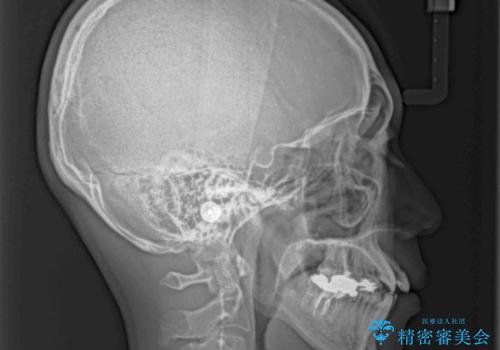

骨格的に下顎骨が上顎骨に対して後退位であったため、上顎の左右第一小臼歯を抜歯し、デコボコを改善するとともに開咬を改善していくこととしました。